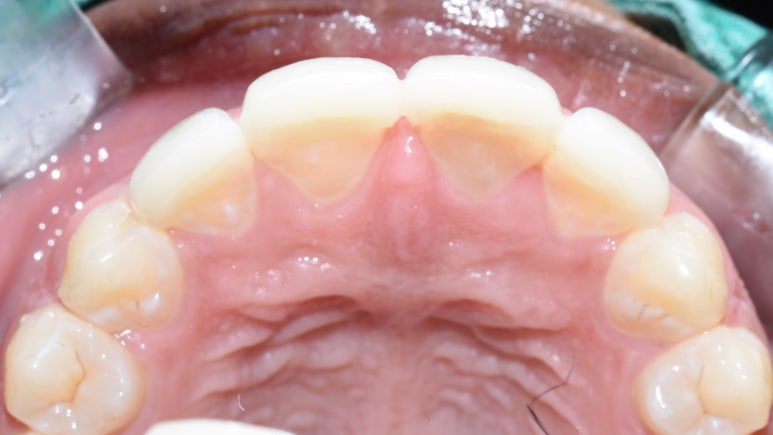

라미네이트는 본 뜬 후 10일 정도 후에 붙였습니다. 치아 삭제는 거의 하지 않았으며 사진상 원래 치아가 깨진 부분만 다듬고 라미네이트를 하였습니다.

간혹 라미네이트가 치아를 너무 많이 삭제한다고 잘못 아시는 분들도 계시는데

많은 분들이 충치때문에 하나씩은 가지고 계신 크라운은 치아머리를 전체적으로 삭제하기 때문에 크라운 보다 앞면만 살짝 삭제하는 라미네이트가 삭제량이 훨씬 적으며

저희 치과에서는 무삭제 또는 튀어나온 부분만 최소삭제하는 라미네이트를 많이 시행하고 있습니다.

치료 전 후

치료 전 후 얼마나 고르면서 치아 겉면 색도 하얗게 되었는지 비교가 되시죠?